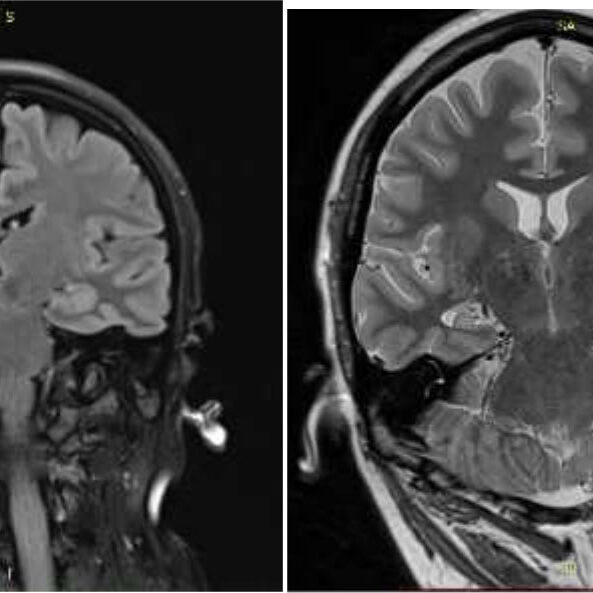

მრგ– მარცხენამხრივი ჰიპოკამპის სკლეროზი

მრგ – ვლინდება ჰიპოკამპის სკლეროზი მარჯვნივ

T2W-TSE FLAIR-T2